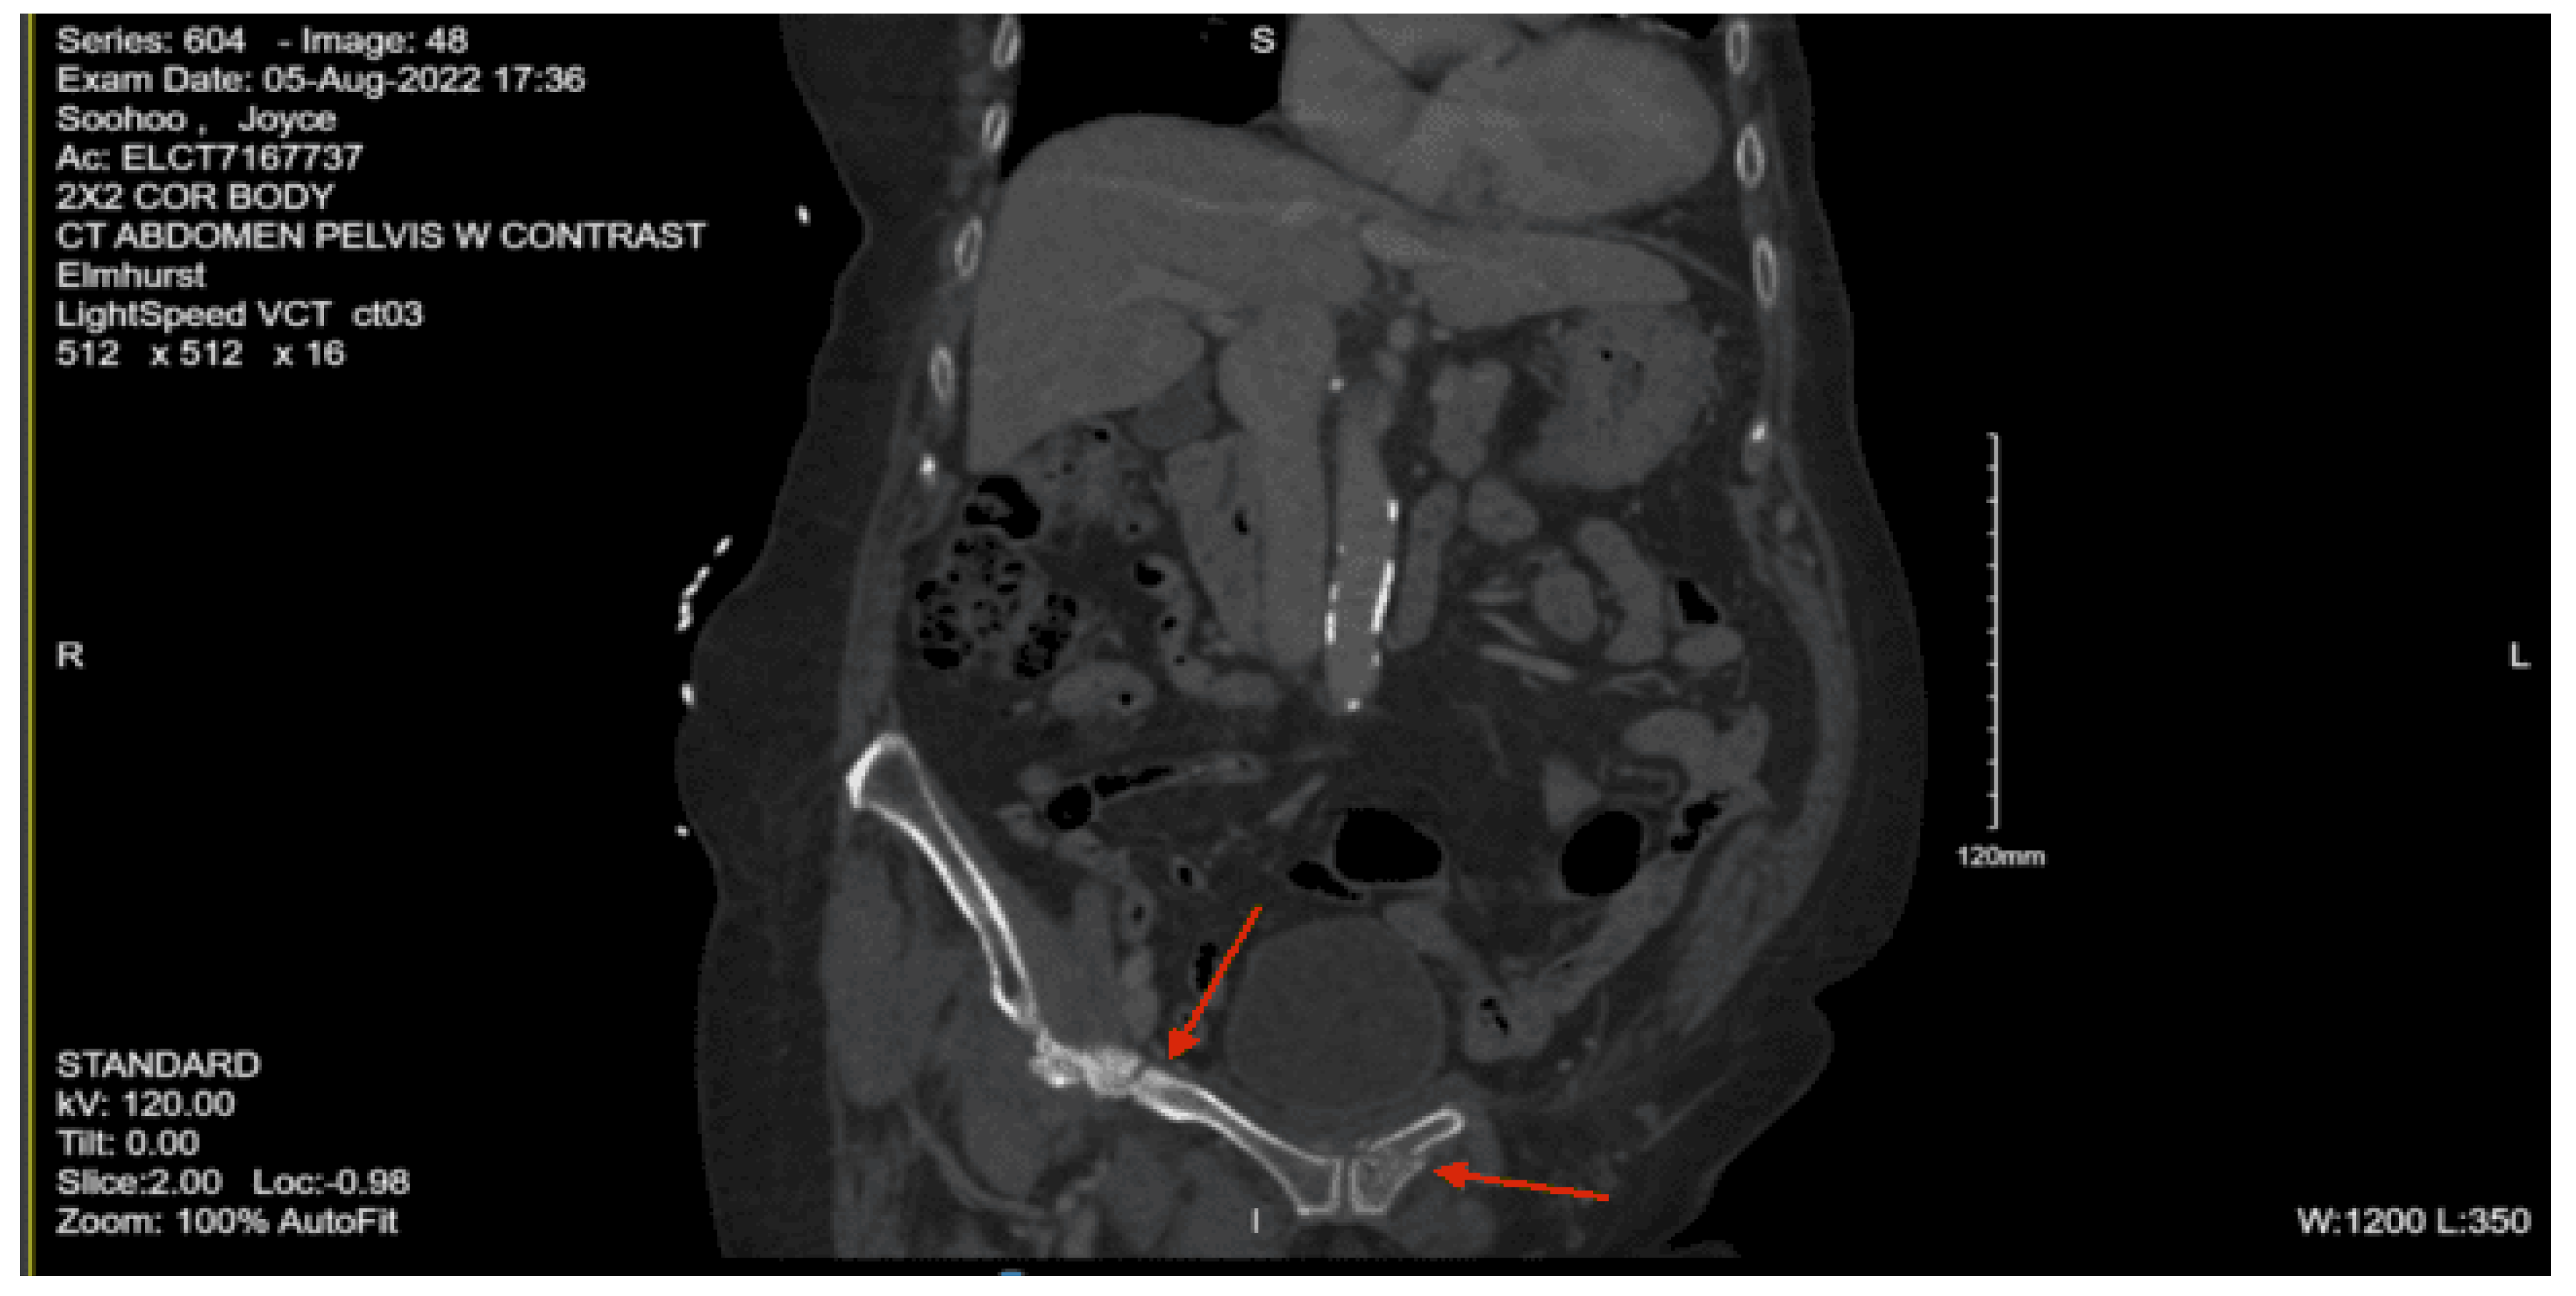

Imaging as shown in Figure 42, Figure 43 and Figure 44:

Portable pelvic x-ray: Possibility of avulsed fracture medial to the left acetabulum and additional fracture at the junction of the left ischium and inferior pubic ramus.

CT abdomen pelvis with contrast: No acute visceral traumatic abnormalities noted. Acute avulsed fracture of the superior-lateral acetabulum and multi-comminuted fractures with distracted bony fragments left in the acetabulum and an acute fracture of the medial aspect of the left superior pubic ramus.